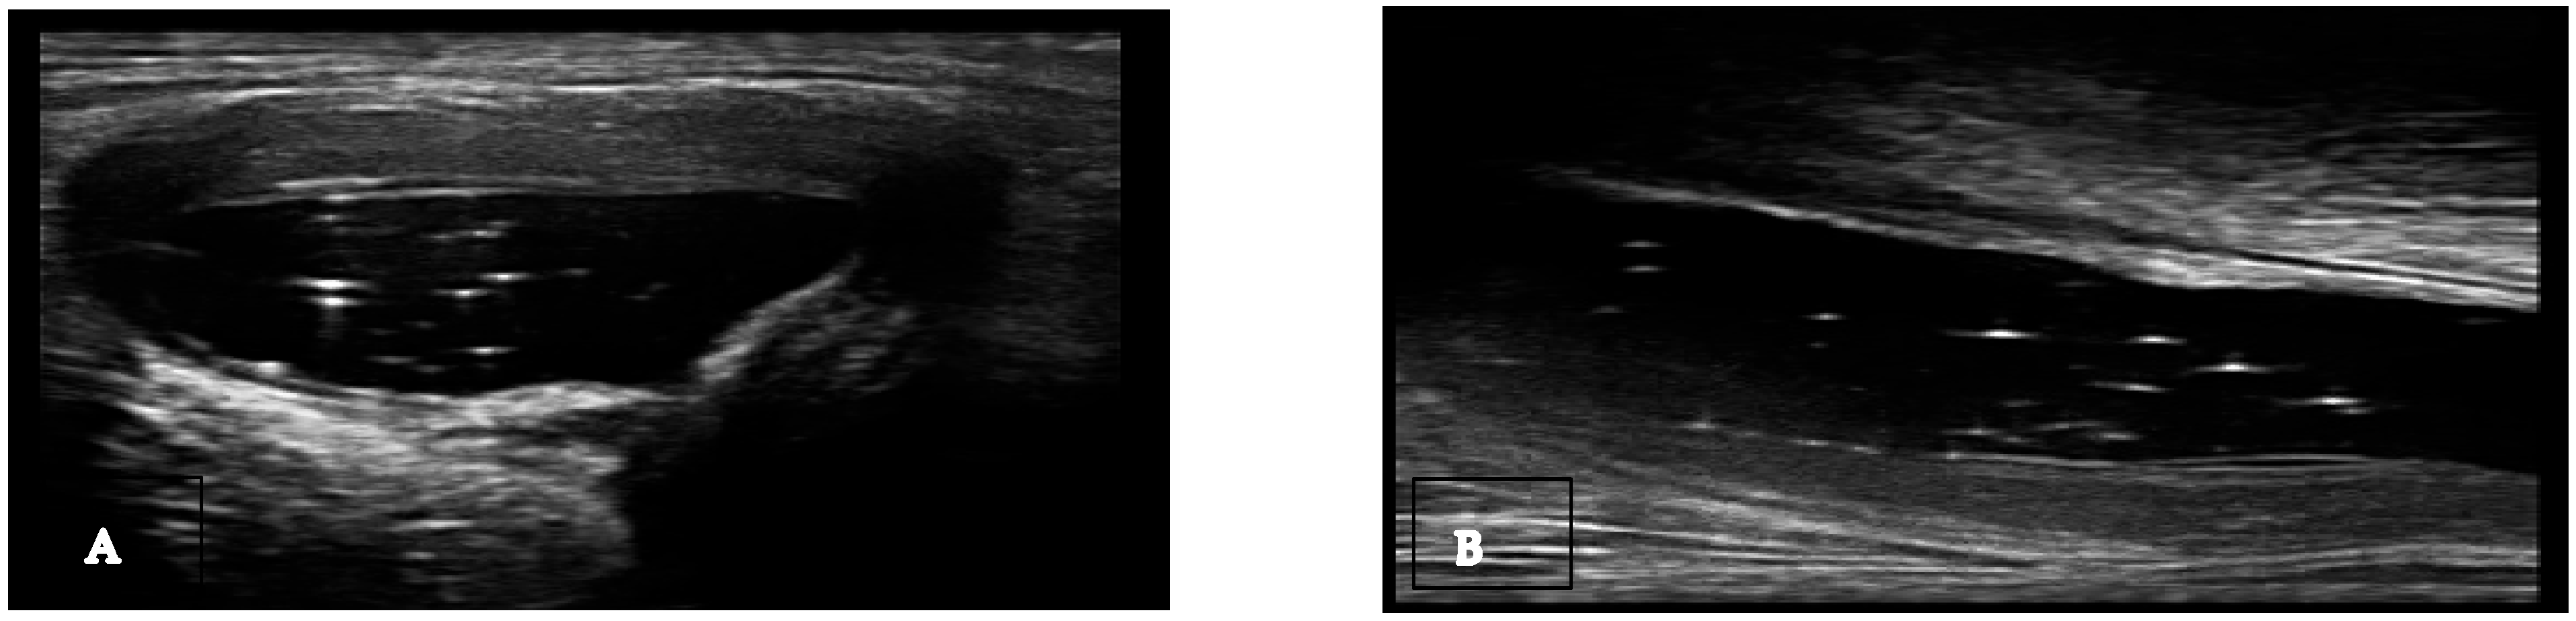

Non-specific signs. Gout is an inflammatory disease that manifests through episodes of acute arthritis. During the progression of the disease, urate arthropathy may occur, accompanied by joint damage. Similar to rheumatoid arthritis and other erosive rheumatism, joint effusion, synovial hypertrophy, and non-specific bone erosions can be found. Joint effusion can be found in gout (Table 1), and the presence of hyperechoic spots (snowstorm sign) in the synovial fluid suggests a crystalline pathology but is not specific to gout (Figure 1) [13]. Synovitis, including Doppler activity, is not considered an elementary lesion for gout because it is not specific enough to define the condition. Synovial hypertrophy and hypervascularization are not specific to gout, but their association with hyperechoic spots (bright focal areas) in the synovium strongly suggests gout. When assessing synovitis and tenosynovitis in gout patients, the definitions validated by OMERACT ultrasound group for rheumatoid arthritis are used. Synovial hypertrophy is another non-specific sign that can be found in gout (Table 1). Tenosynovitis is defined as hypoechoic or anechoic thickened tissue within the tendon sheath, with or without fluid, seen in two perpendicular planes and potentially exhibiting a Doppler signal [11,12,13].

Figure 1.

Baker cyst in transverse (A) and longitudinal (B) view with the presence of multiple hyperechoic spots “snowstorm sign”.